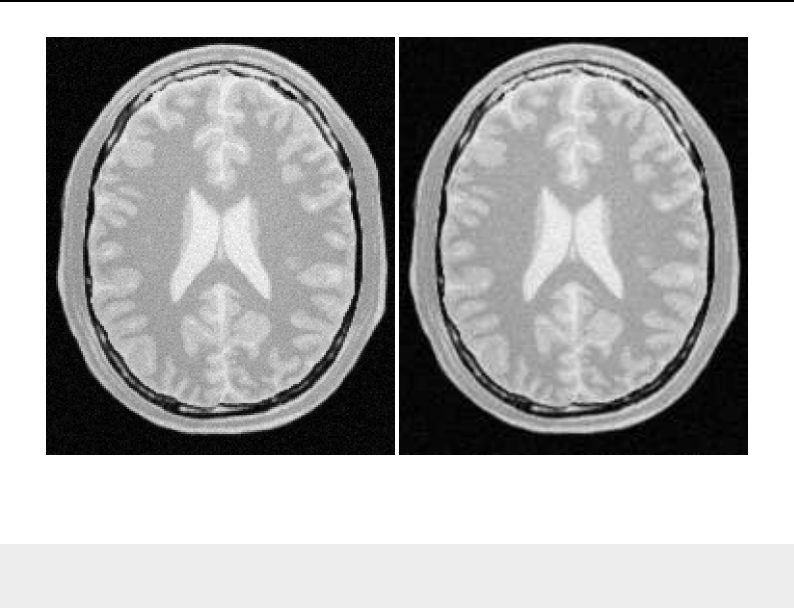

The National Library of Medicine Insight Segmentation and Registration Toolkit, shortened as the

Insight Toolkit (ITK), is an open-source software toolkit for performing registration and segmenta-

tion. Segmentation is the process of identifying and classifying data found in a digitally sampled

representation. Typically the sampled representation is an image acquired from such medical instru-

mentation as CT or MRI scanners. Registration is the task of aligning or developing correspondences

between data. For example, in the medical environment, a CT scan may be aligned with a MRI scan

in order to combine the information contained in both.